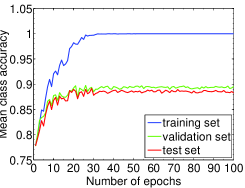

We highlight that training-relevant hyper-parameters can significantly affect the convergence of cost function, the learning speed and the generalization capability of the network. Their impacts are demonstrated via the learning curves of MCA on training, validation and test sets shown from Fig. 4 to Fig. 8. In each figure, we focus on one hyper-parameter while the others are set to their optimal values in Table 2.

Fig. 4 LABEL:sub@subfig:lr1 indicates that when learning rate is small, e.g., , the learning process is so slow that the MCA of the three sets have not become stable in epochs. Properly increasing the learning rate effectively improves learning efficiency and the MCA becomes stable in epochs, as shown in Fig. 4 LABEL:sub@subfig:lr2. At the same time, an over-large learning rate, e.g., , will destabilize the learning process and degrade the classification performance. Also, Fig. 5, 6 and 7 demonstrate the impacts of mini-batch size, momentum and weight decay, respectively.

The comparison in Fig. 8 shows that the dropout strategy (Hinton et al., 2012) shall be used cautiously. When dropout with ratio of (randomly setting the activations to zero with probability of ) is applied to the first fully-connected layer of our CNN system, the learning process becomes slow and fluctuated on ICPR2014 cell dataset. A stabler and faster learning process without overfitting on the test set is gained when removing dropout, as well as better classification performance. This indicates that the neurons at the first fully-connected layer may have to work together to distinguish different staining patterns. In light of this, we decide not to employ dropout when training our network on ICPR2014 dataset.